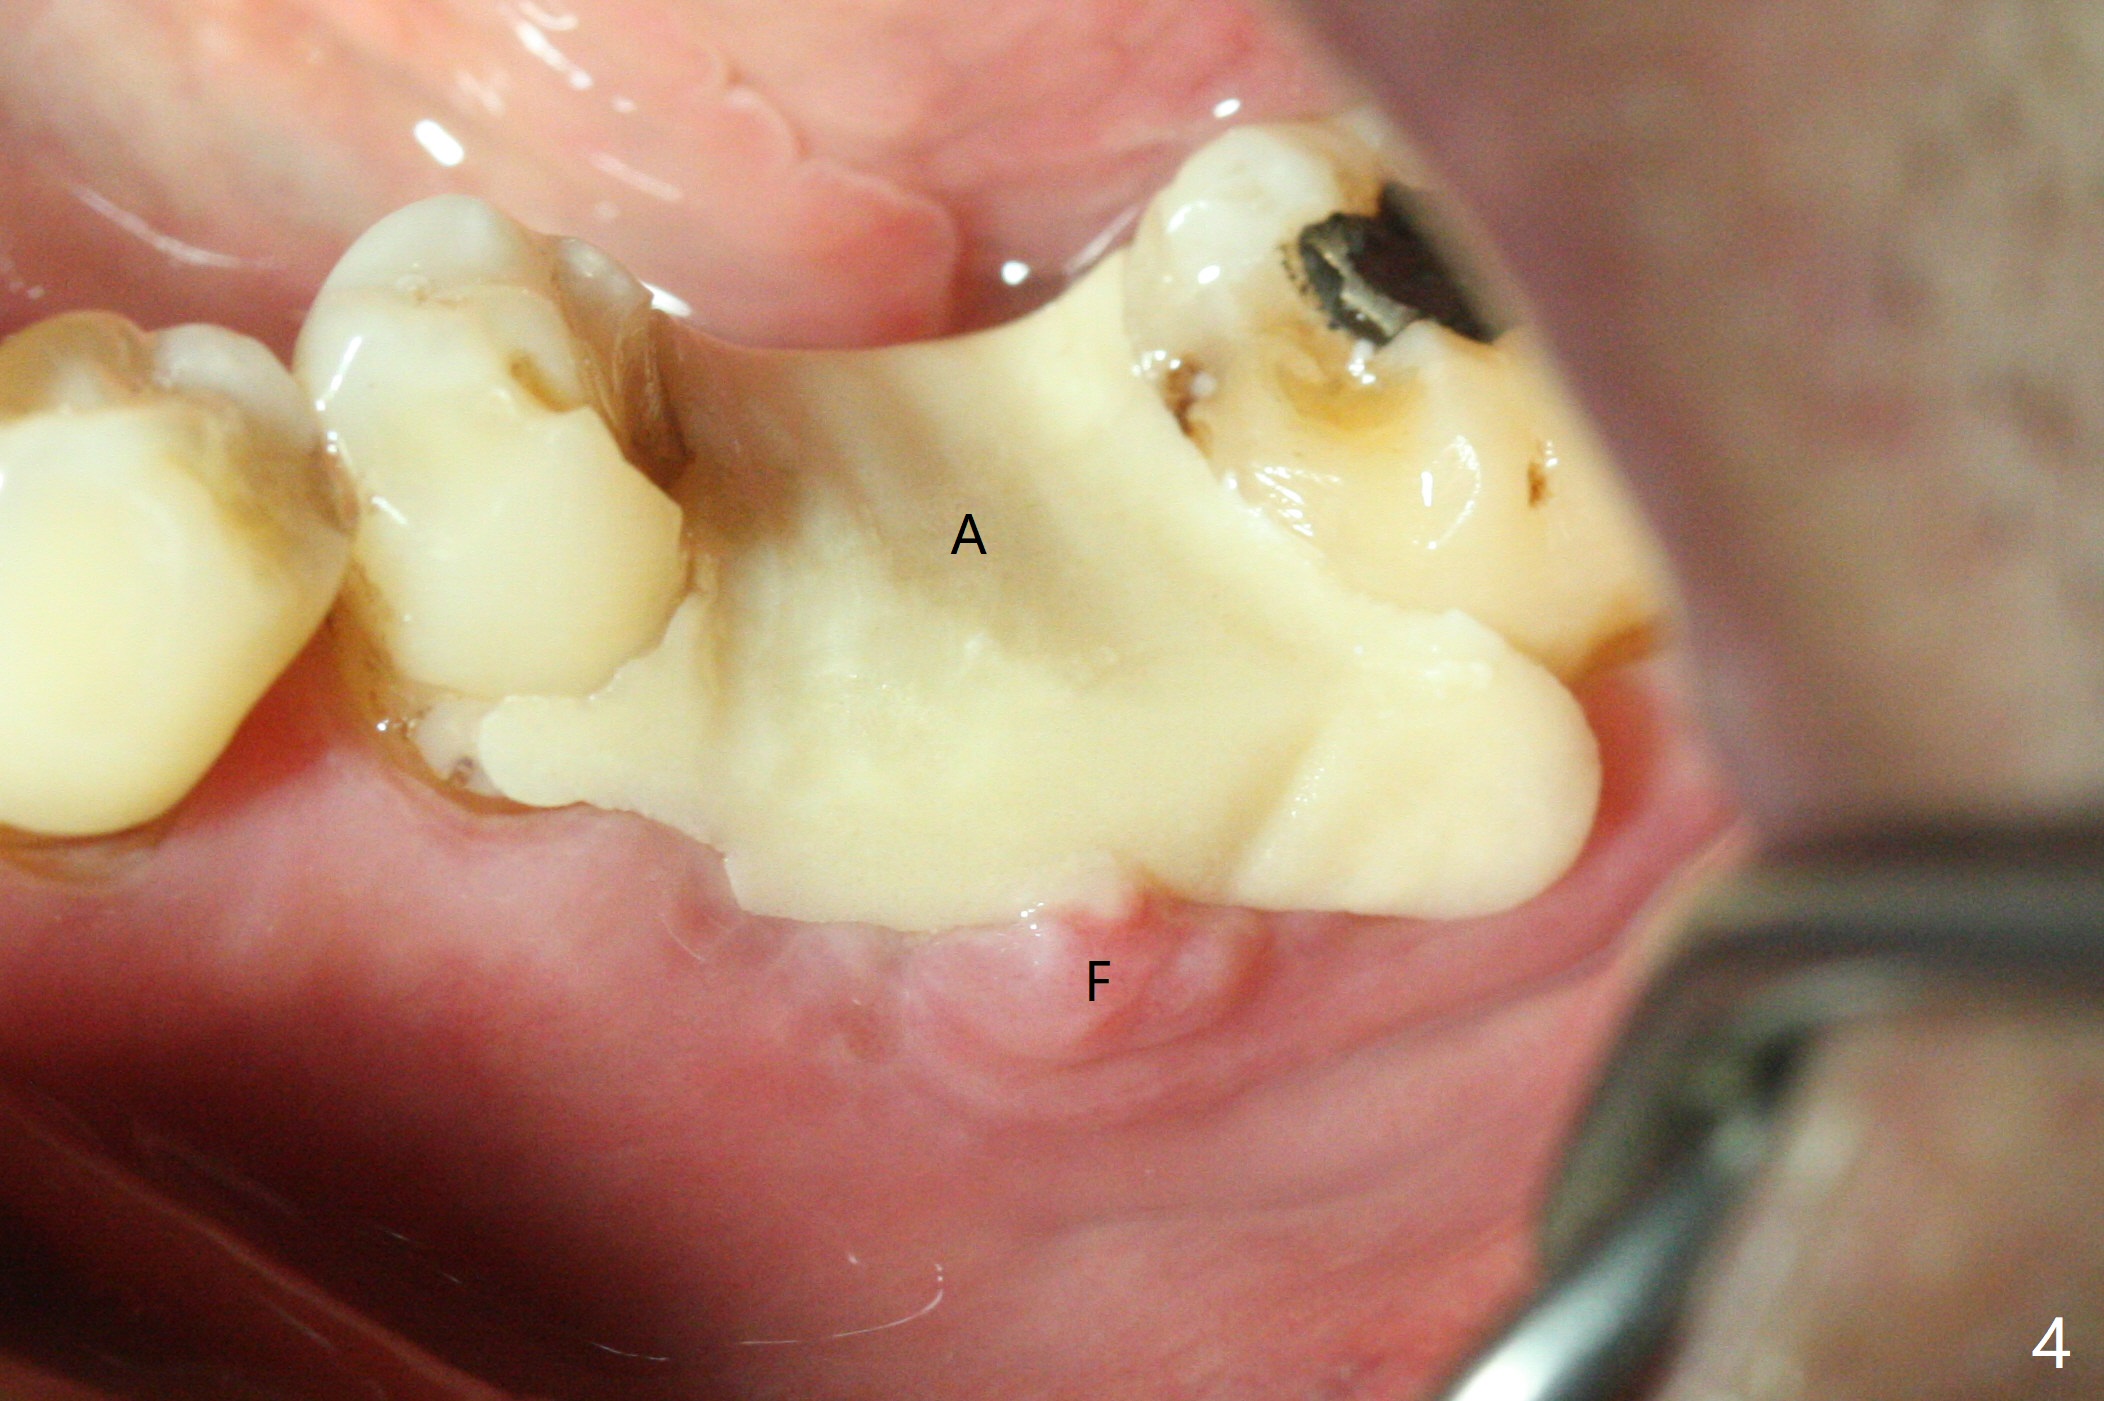

A 73-year-old man (with history of lung cancer with chemotherapy 6 years ago) requests removing the tooth #19 (Fig.1) with the loose mesiolingual fragment (Fig.2 ML). The mesiobuccal plate is low when the tooth is extracted. The septum should provide additional blood supply to bone graft to facilitate healing (Fig.3 S, as compared to the case without it). After placement of 6-month membrane and suturing, acrylic dressing is applied, which is stable 9 days postop (Fig.4 A). The acrylic dressing remains in place 1 month postop (Fig.5). After wiggling, it dislodges fairly easily. The socket heals with slight atrophy (Fig.6).